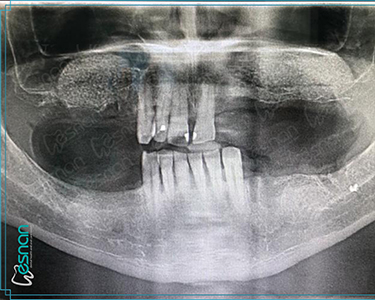

Oral symptoms usually have underlying bone and skeletal structures beneath the soft tissues. Radiographs can reveal structures that are not clinically visible, helping dentists to deal with many unidentified problems. The advantages and applications of oral, dental, and maxillofacial radiology can be listed as follows:

Oral, dental, and maxillofacial radiology is an indispensable tool in diagnosing and treating various conditions that affect the mouth, teeth, and jaws. Through radiographs and other imaging modalities, dental professionals can visualize structures not readily visible during a clinical examination. This allows for early detection of dental caries, periodontal disease, infections, tumors, cysts, and developmental anomalies, among others. Early diagnosis and accurate assessment through radiographic imaging are crucial for determining the most appropriate treatment course, leading to improved patient outcomes and overall oral health.

Each examination listed above serves a specific purpose in dental diagnostics. Panoramic X-rays provide a broad view of your teeth, jaws, and surrounding structures, while intraoral radiography offers detailed images of individual teeth. Cephalometric X-rays assess facial growth and development, and CBCT scans provide detailed 3D images for complex cases like implant planning and oral surgery. Our experienced team is dedicated to utilizing these technologies to deliver precise and personalized care for every patient.